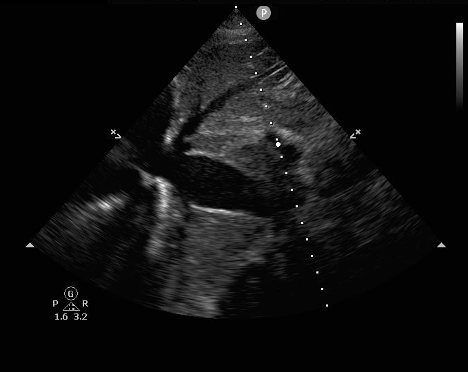

Ultrasound exam for cardiac tamponade must logically start with identification of a pericardial effusion. Emergency medicine physicians have shown that they can use point of care ultrasound with high sensitivity and specificity to find effusion.3 Acute effusions, such as in trauma, can be significant even when very small. If the pericardial space does not have time to stretch and accommodate the new fluid, pressure will rise quickly as it is inversely related to the volume the fluid occupies. The identification of any pericardial effusion in a hypotensive trauma patient should be considered evidence of tamponade until proven otherwise. Chronic effusions, however, can become very large before the development of tamponade physiology.4

Figure 1: Pericardial effusion